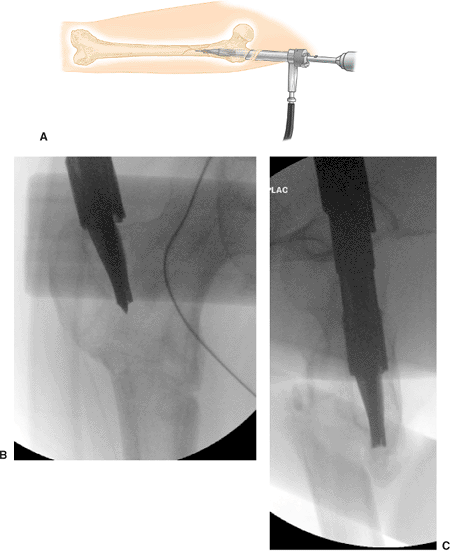

![]() |

|

Figure 20.30. Channel reamer insertion schematic. A. Insertion of channel reamer. B. Radiograph AP. C. Radiograph lateral.

The channel reamer assembly is introduced over the tip-threaded guide

wire and advanced 1 to 2 cm into bone. The reamer assembly is then

manipulated under image guidance until the shaft axis and intended path

of the reamer form an angle of approximately 5 degrees in the AP view

and is in line in the ML view. The tip of the reamer should be directed

to a point just inferior to the normal location of the lesser

trochanter as seen on the AP view. Once the correct orientation is

obtained, the reamer assembly is advanced to full depth so that it

contacts the proximal end of the entry portal tool (Fig. 20.30).